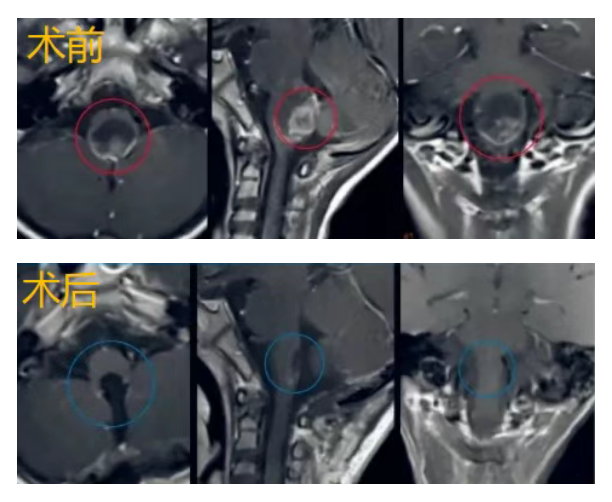

经过INC巴教授的精细主刀,采用枕下后正中入路,在术中神经电生理监测下,手术成功实现了脑干(延髓段)肿瘤肉眼下全切,手术顺利,星星安全醒来。受压的延髓逐渐复原,术后第一天星星的肢体功能正常,术后17天,成功出院。